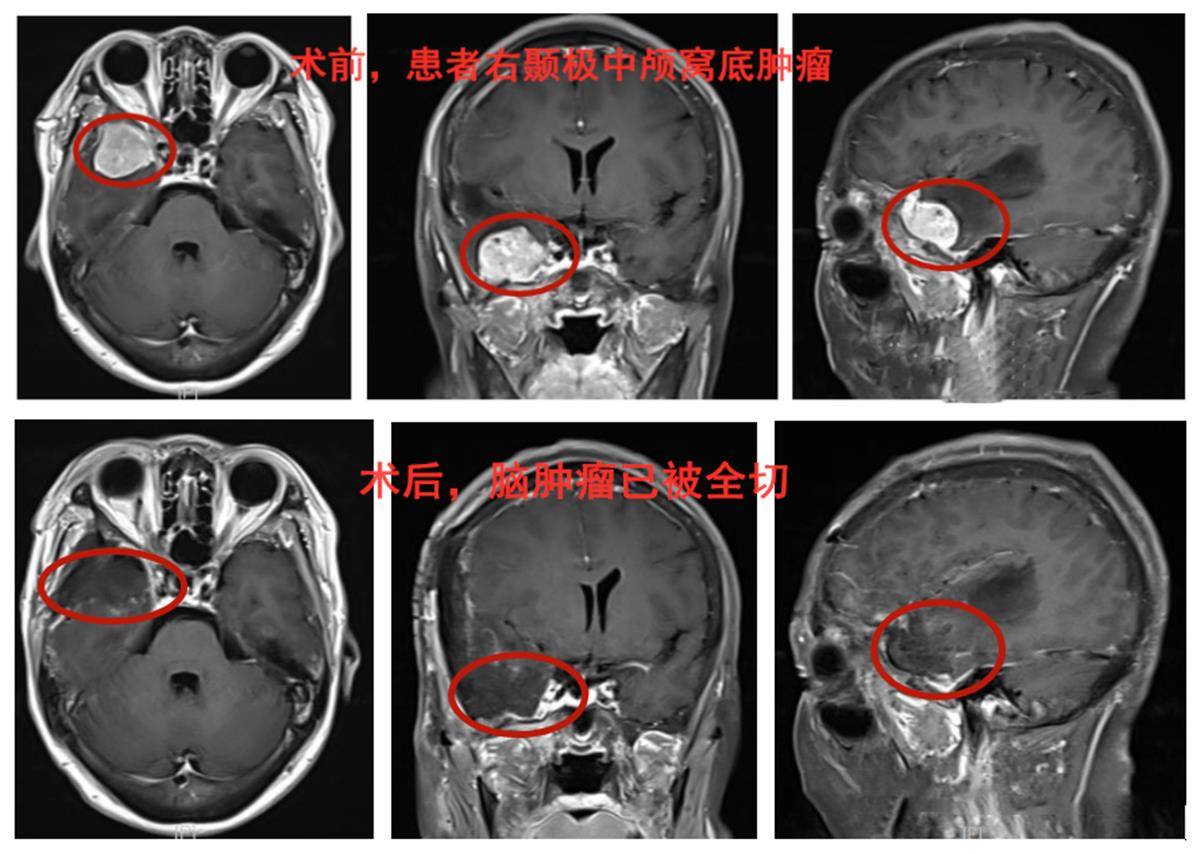

医生在脑部CT影像上观察到刘女士右侧中颅窝底部有异常团块样物。该院功能神经外科王焕明教授认为,刘女士并非脑梗,而脑肿瘤的可能性更大。刘女士接受头部核磁检查后,结果印证了医生的初步判断——刘女士右侧中颅窝底确实存在脑肿瘤。

随后,王焕明带领团队为刘女士完成了皮层电极监测下的开颅手术。术后病理提示为良性脑膜瘤。术后次日,刘女士就可下床自由活动。一周以来,她的记忆力显著恢复,即将康复出院。